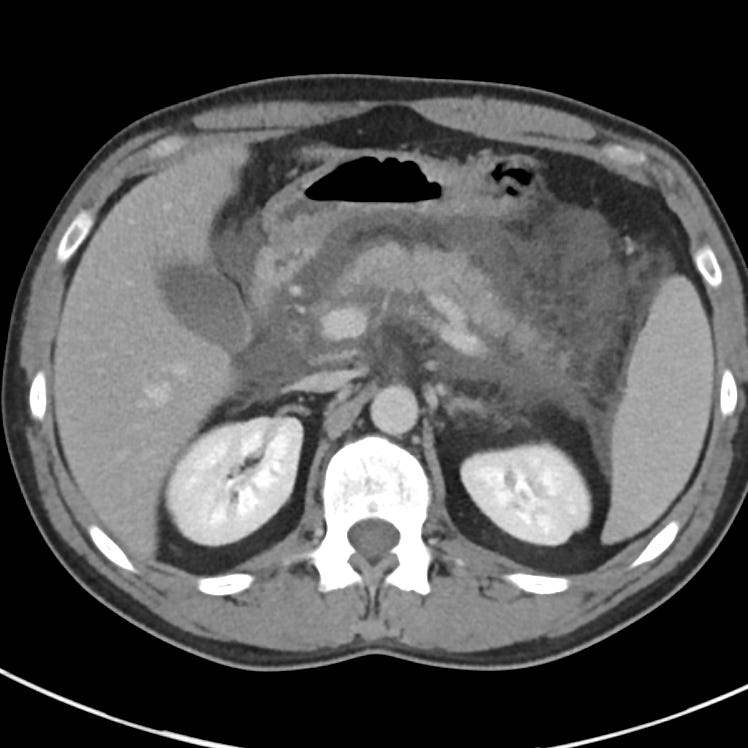

A 14-year-old female presents for severe, diffuse abdominal pain over the last 2 days. Patient states that the pain is worse with movement and improves when she lays still. The patient endorses nausea, vomiting, and d...